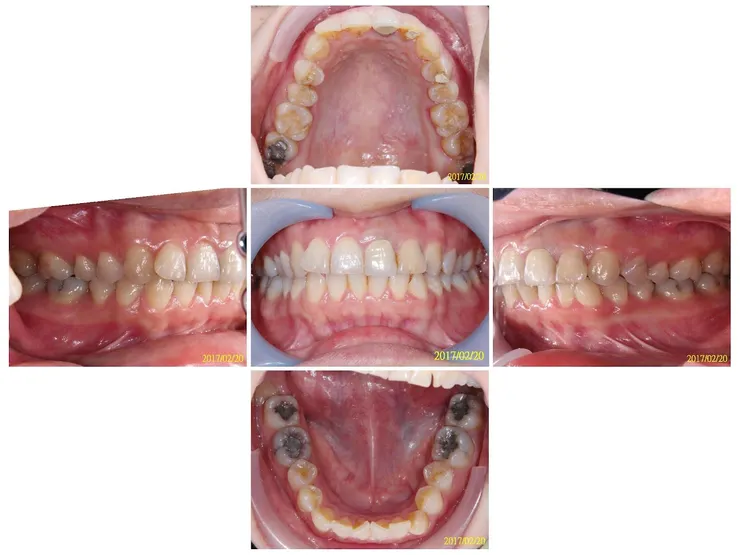

口內照是共通點,都要照的

• 擴大板(是重點,不要忘了照,正反面都要照,有時會反光看不清楚,可以多照幾張)

每種功能性矯正裝置所咬拍攝的點,不一樣喔 口內照是共通點,都要照的 擴大板(是重點,不要忘了照,正反面都要照,有時會反光看不清楚,可以多照幾張) MRC、EF、PreOrtho等彈性裝置(裝置不用照),除了口內照,再請加以下這兩張 反向面弓(如有,請加拍正/側面,有戴裝置2張,沒有時(素顏)2張)